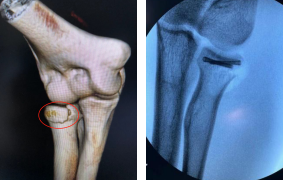

术前(左图)术后即刻(右图)

本例患者于1年前摔倒,致右肘畸形、活动受限,伤后在当地医院进行了外固定治疗,后右肘僵硬,活动受限。来院查体显示其右肘关节45度僵硬,不能活动。腕、肘关节微创修复外科(手外二病区)胡俊生副主任医师征得患者同意后为他安排了肘关节镜下微创手术。第二天,胡医生手术团队为患者进行了关节镜下右肘关节腔、滑膜清理、关节松解、神经松解术,术后即刻患者被动恢复运动范围,术后借助肘关节cpm机进行康复锻炼,二期再行神经松解术,尽量让其恢复部分主动功能。